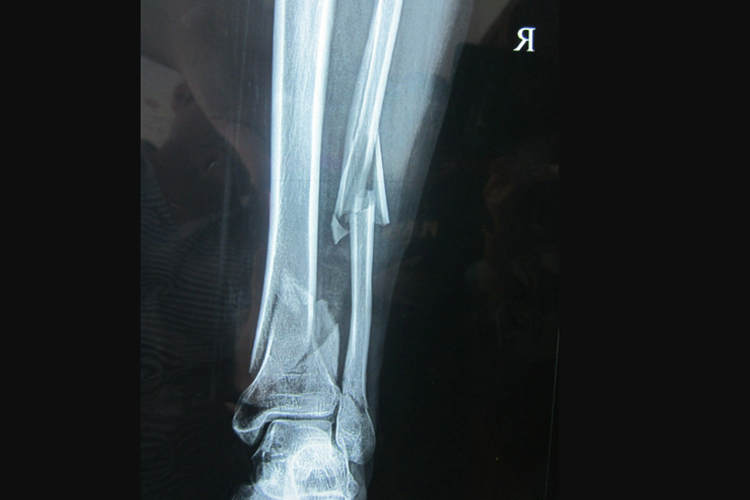

小腿骨折一般指的是胫腓骨骨折,临床常见骨折部位的疼痛、肿胀、畸形。

小腿骨折的主要症状是疼痛、肿胀、畸形和功能障碍。骨折后患肢有剧烈疼痛,尤以活动时加剧。对于儿童症状较轻的骨折、成人的单纯腓骨骨折,局部肿胀、压痛程度相对较轻,活动受限不明显,甚至可以行走。如骨折有明显的移位,可表现为小腿的畸形、反常活动,有骨擦音、骨擦感。

高能量暴力造成的严重软组织破坏、神经血管损伤、粉碎骨折、骨缺损,这种高能量暴力常导致肢体多种组织严重创伤,肢体存活困难。